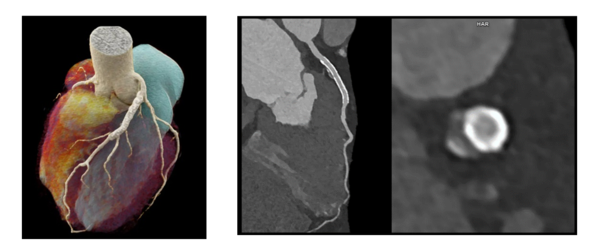

三重大学大学院医学系研究科 放射線医学教室 教授 佐久間 肇氏は,「従来のCTの解像度(0.5-0.6mm)では直径2-3mmの冠動脈の狭窄や血管壁の動脈硬化病変を正確に捉えることはできませんでした。Dual Source CTの高いシャッタースピード(66ミリ秒)とフォトンカウントティング検出器による従来比約10倍の空間解像度を組み合わせることで,心臓画像診断の“Precision Medicine“がはじめて実現できます。フォトンカウンティングCTの画像は超解像度(1024x1024x0.2mm)ですので,一回のCT検査でHD映画一本分を超える多量のデータが発生します。三重大学病院では世界で初めて,すべての診察室と病棟でフォトンカウンティングCTの超解像度画像を表示できるシステムを開発し,地域の皆様の診療に直接役立てています。」と述べている。

「NAEOTOM Alpha」で撮影した心臓画像エラスムスメディカルセンター 提供